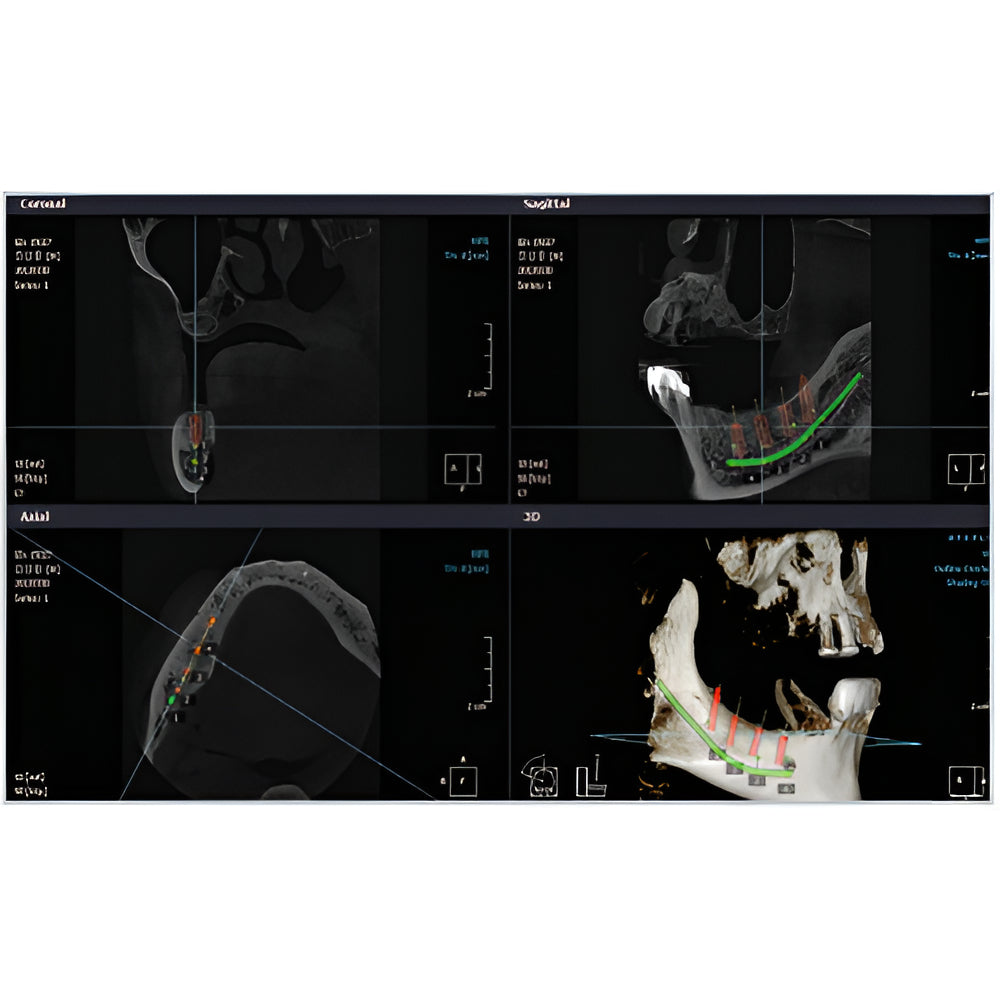

Rayscan Alpha brings another innovative technology with less Recon time and bigger FOV Size. And there are also new features – Fast scan mode, Object scan and Multi FOV.

- Field Of View: 9x9

- 2D/3D Imaging Software with License

- Multiple Scan Modes

- Adaptive Moving Focus Technology